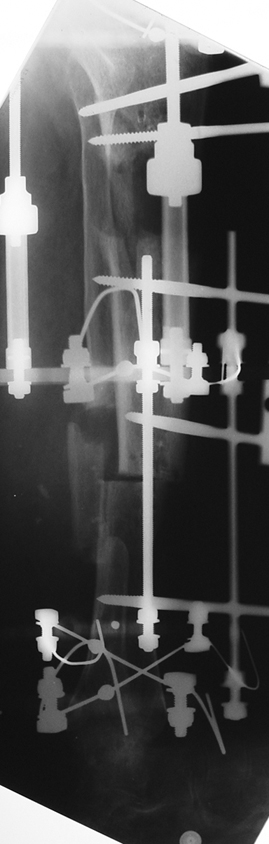

Appropriate radical debridement necessitates excision of all necrotic bone and soft tissues, and frequently causes instability at the involved extremity. The remaining bone and soft tissue defect has to be fixed and reconstructed. The distraction osteogenesis method of Ilizarov is used successfully for achievement of union, correction of the deformity, elimination of limb length inequality and reconstruction of segmental bone defects.

The duration of external fixation (external fixation index) depends on the amount of distraction required, and the extremity is prone to complications during this period. After the distraction phase is completed, the external fixator remains in place during the consolidation phase, which lasts twice as long as the distraction phase; but this period is hardly tolerated. If the external fixator is removed before sufficient consolidation is achieved, fractures, deformity and shortness will be the result. In our department, ‘lenghthening over nail’ method is used in order to decrease the external fixation index and increase patient comfort and activity level. In this method, the intramedullary nail is statically locked after the completion of the distraction phase, and external fixator is removed. The extremity is stabilized by the intramedullary nail during consolidation phase. In this way, complications due to long external fixation index or early removal of the external fixator are avoided.